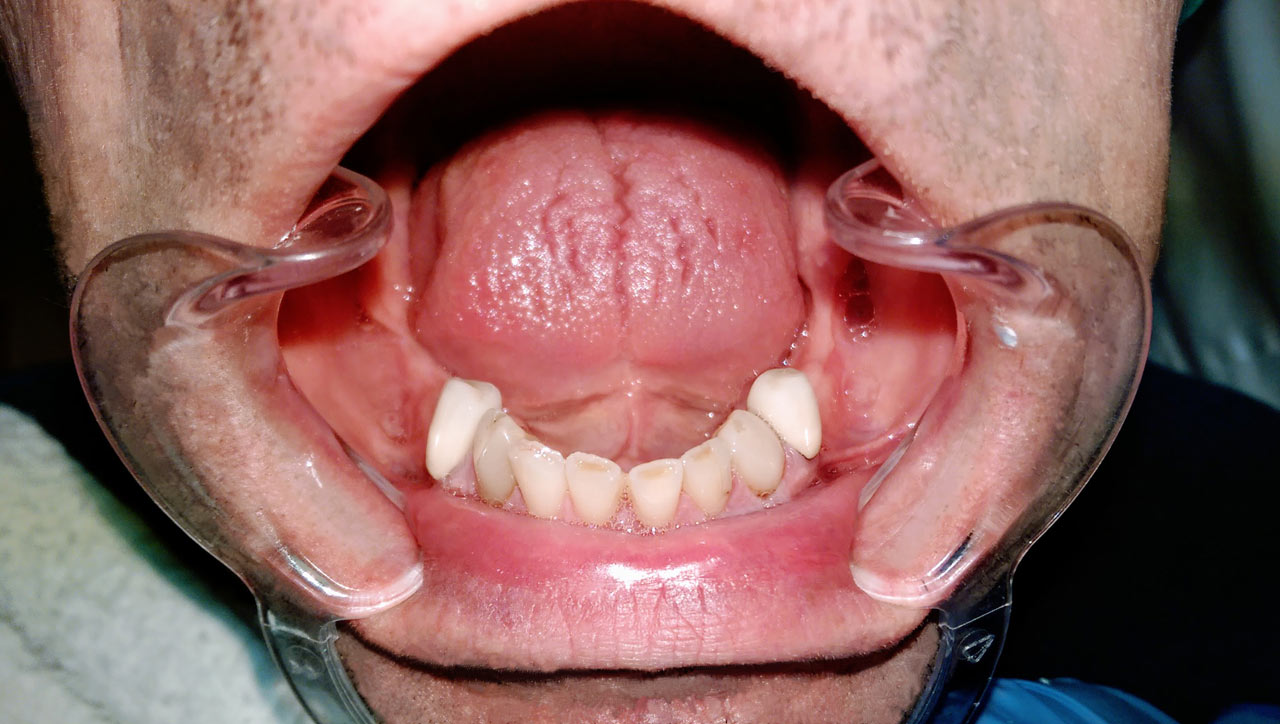

Alsó állcsont teljes rehabilitációja 72 óra alatt

Alsó állcsont teljes rehabilitációja 72 óra alatt, azonnal terhelhető implantátumokkal súlyos paradontitisben szenvedő dohányzó páciens esetében. Az alsó állcsont fogai mind mozogtak az előrehaladott fogágypusztulás miatt.

A fogakat eltávolítottuk, a gyulladt, fertőzött csontot kitakarítottuk, kifertőtlenítettük, majd azonnal implantáltunk.

Svájci, IHDE márkájú, azonnal terhelhető implantátumokat helyzetünk be, és ezekre harmadnapra rögzített, hosszútávú, fémvázas, esztétikus műanyaggal leplezett hidat ragasztottunk be.

Ezt az ideiglenes hidat a sebek gyógyulása miatt használjuk, de tartóssága miatt véglegesként is használható.

A legtöbb esetben, ahogy itt is, 6 hónap múlva porcelán hídra cseréljük, a teljes gyógyulás után.